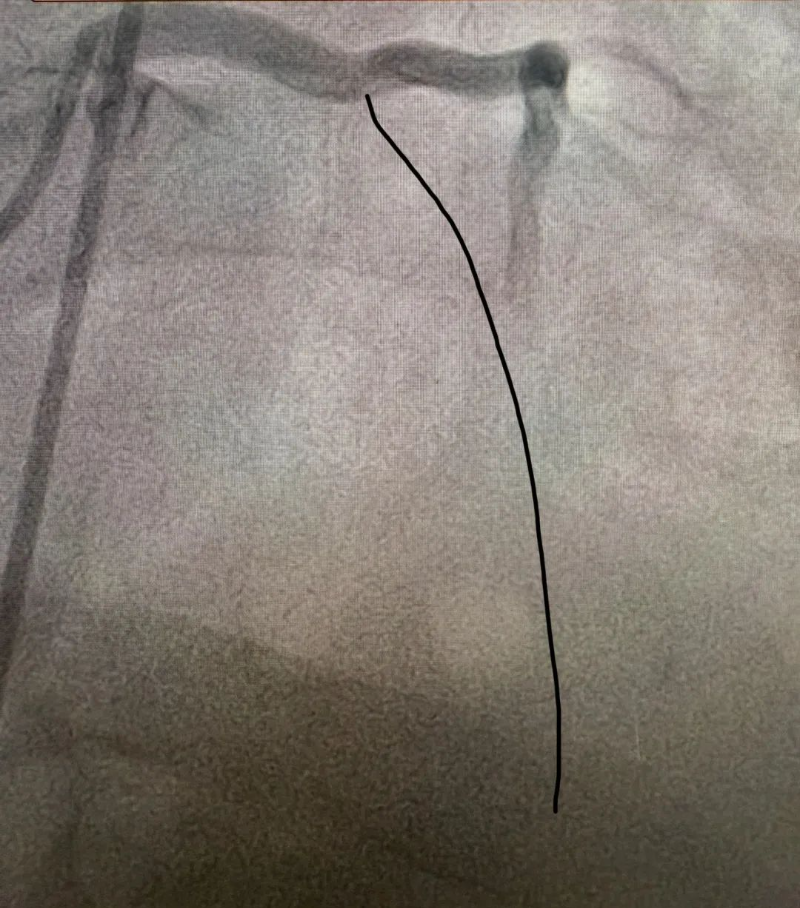

造影見前降支

開口就完全閉塞